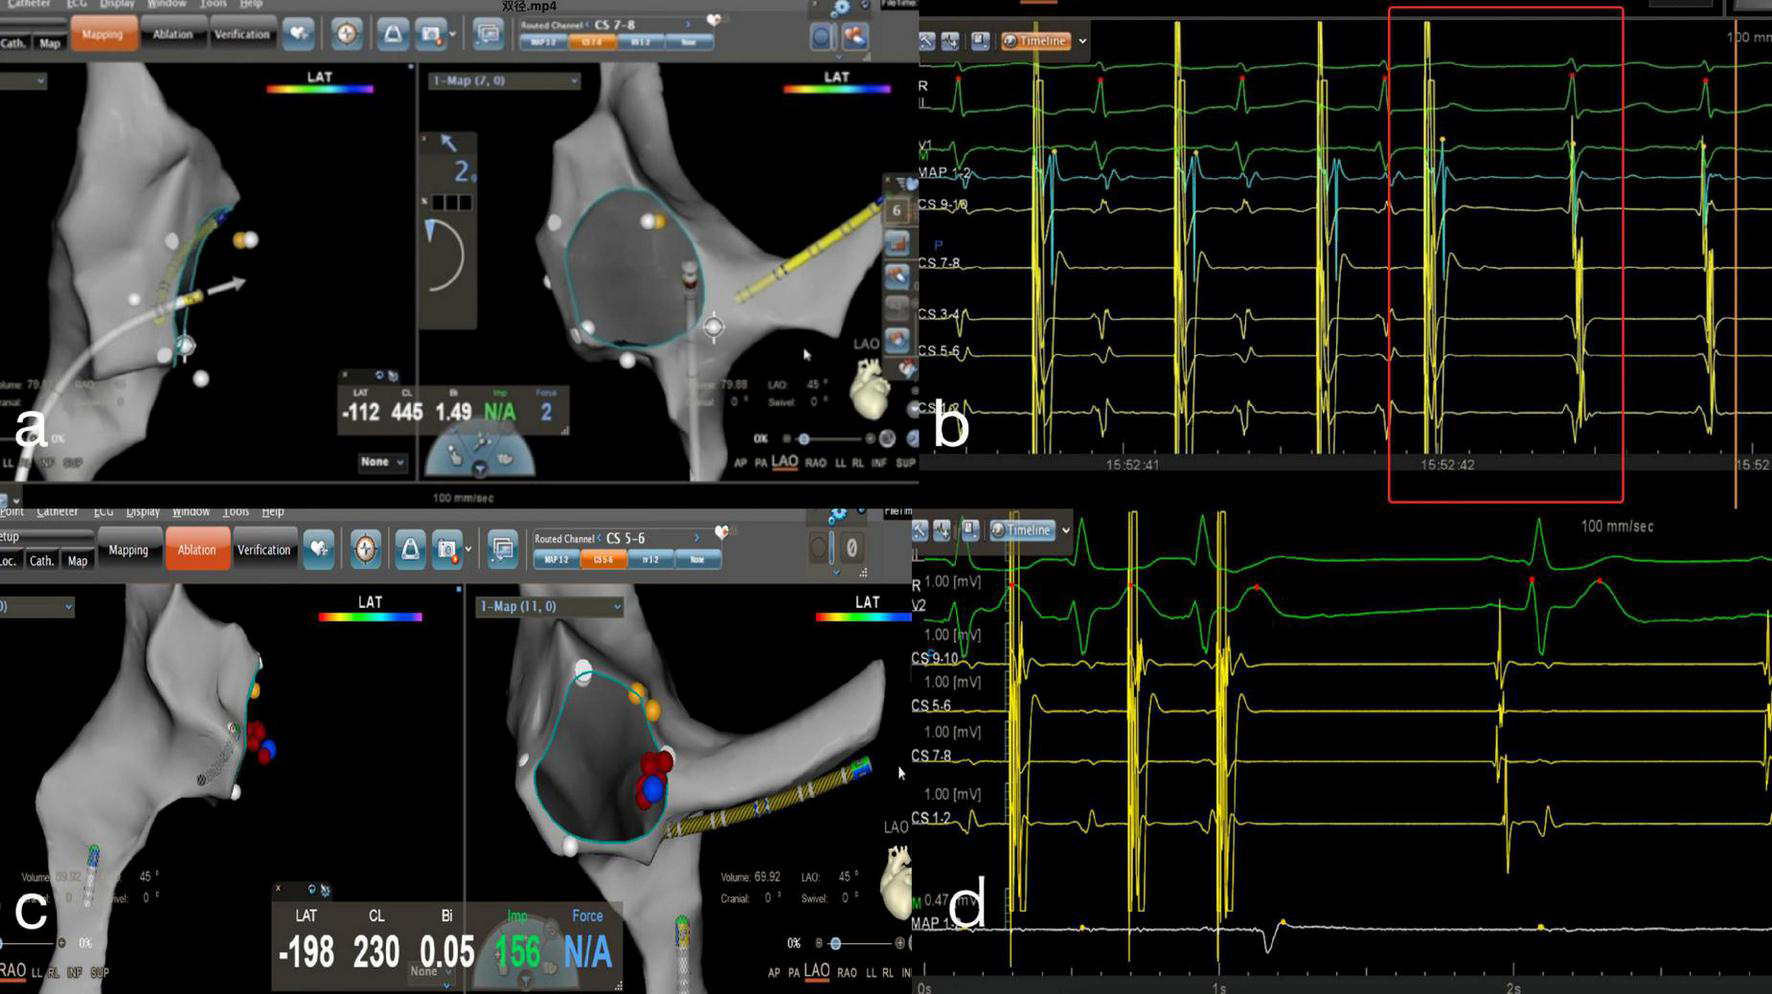

FIGURE 3

Zero-fluoroscopy radiofrequency ablation for AVNRT. (a) Modeling of the right atrium was performed with a Decanav catheter using CARTO 3 system. The Decanav catheter the apex of the right ventricle. (b) An electrophysiology study showed AH/AV jumping. The slow-fast type of AVNRT was diagnosed. (c) The level of the lower portion of the coronary sinus ostium was suggested to be the slow pathway location. (d) AV node jumping disappeared, and AVNRT was not induced. AV, atrioventricular; AVNRT, AVNRT, atrioventricular nodal reentrant tachycardia.

The following procedures were followed for AVRT. The ablation targets in an overt accessory pathway were those with the earliest ventricular activation (EVA) and/or the retrograde earliest atrial activation (EAA). The ablation target in a concealed accessory pathway was the retrograde EAA (i.e., local fusion of V and A waves, or at the time of no conduction delay in the accessory pathway, a local VA interval ≤ 40 ms). The EVA was more than 20 ms earlier than the earliest δ wave on the body surface at the start of the local V wave, the AV interval in the local electrogram ≤ 40 ms without conduction delay in the accessory pathway, or the A and V waves fused (equipotential line between A and V waves ≤ 5 ms). Ablation was performed in cold saline power mode with an energy of 30 W and a cut-off temperature of 45°C. The accessory pathway was blocked within 10 s, resulting in an impulse duration of 60–120 s. A left-sided accessory pathway required either a trans-septal approach under the guidance of ICE or a retrograde transaortic approach. The ablation target and ablation mode were confirmed in the same way as for the right accessory pathway. Figure 4 displays the RFCA procedure for AVRT under zero-fluoroscopy guidance.

FIGURE 4

Zero-fluoroscopy radiofrequency ablation for AVRT. (a) Modeling of the right atrium was performed with a Decanav catheter using the CARTO 3 System. The Decanav catheter was placed in the coronary sinus and a quadripolar catheter was placed in the apex of the right ventricle. (b) During the onset of SVT stimulated by S1S1, the retrograde A wave showed eccentric conduction and was diagnosed as a left concealed accessory pathway. (c) The retrograde aortic method was used to deliver the ablation catheter to the aortic root and establish a model of the aorta. (d) The ablation catheter electrode crosses the aortic valve to model the mitral annulus, and the ablation target is located at three o’clock. (e) An electrophysiology study showed ventricular pacing with ventricular-atrial separation and retrograde transmission through atrioventricular node. The retrograde A wave was centripetal.